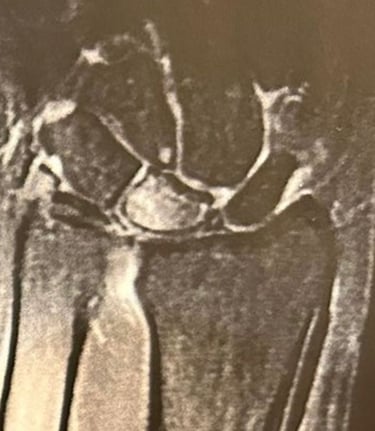

Kienböck

É uma doença progressiva caracterizada pela osteonecrose (morte do tecido ósseo) do osso semilunar, localizado no punho.

Tem origem multifatorial e seu diagnóstico depende de exame clínico e de imagem, como radiografias e ressonância magnética.

O tratamento varia conforme o estágio da doença e pode incluir alívio da carga sobre o osso, revascularização ou procedimentos cirúrgicos mais complexos para preservação do punho.